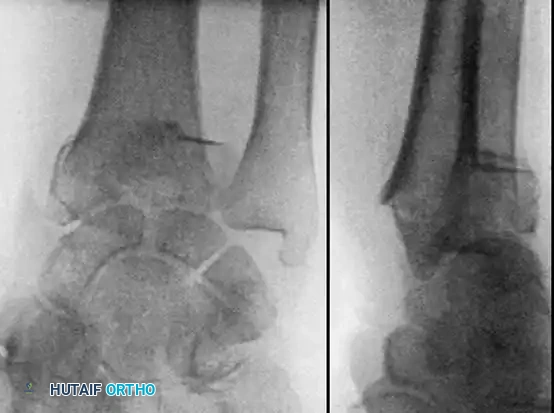

Type II distal radial shear fractures (Barton type) usually require ORIF. These fractures are almost impossible to treat by closed means. Buttress plate fixation of volar Barton fractures is the gold standard.

Type III compression injuries require operative treatment if intraarticular damage is significant or radial shortening is severe. Careful restoration of the articular surface, radial angulation, and length is crucial. Fixation with multiple K-wires or plates is often necessary, and cancellous bone grafting is frequently required to fill impacted metaphyseal voids.

Often, a combination of open and closed techniques is necessary to treat Type III fractures satisfactorily.

Fig. 54-103 A and B, Four-part type III distal radial fracture treated by open reduction, internal fi xation of intraarticular component, iliac bone grafting, and external fi xation. C and D, Follow-up radiographs at 5 weeks (C) and 3 years (D) show anatomical restoration of joint surface, maintenance of radial length, and absence of degenerative changes. (From Fernandez DL: Fractures of the distal radius: operative treatment, Instr Course Lect 42:73, 1993.)

Fig. 54-103 A and B, Four-part type III distal radial fracture treated by open reduction, internal fixation of intraarticular component, iliac bone grafting, and external fixation. C and D, Follow-up radiographs at 5 weeks (C) and 3 years (D) show anatomical restoration of joint surface, maintenance of radial length, and absence of degenerative changes.